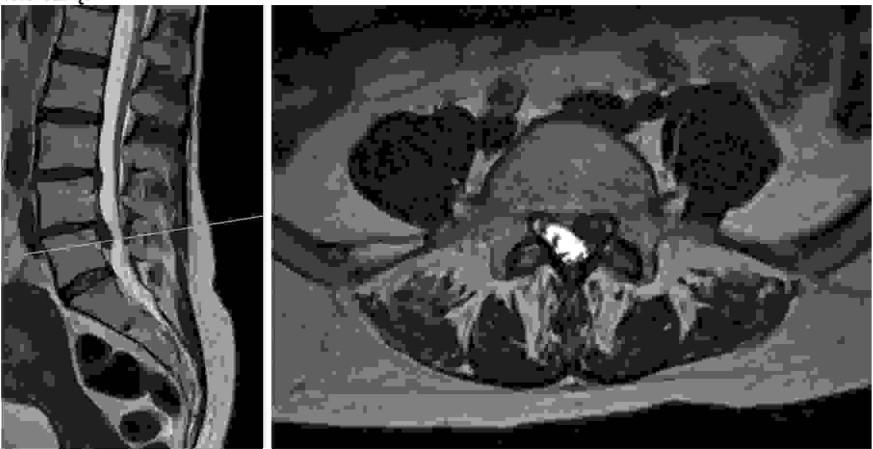

Do charakterystycznych objawów podmiotowych i przedmiotowych patologii widocznej na poniższych obrazach tomografii rezonansu magnetycznego należą: 1) ból okolicy lędźwiowej, 2) ból promieniujący do kończyny dolnej wzdłuż przedniej powierzchni uda, 3) objaw Lasegue'a, 4) osłabienie siły zgięcia grzbietowego stopy, 5) osłabienie zgięcia podeszwowego stopy.